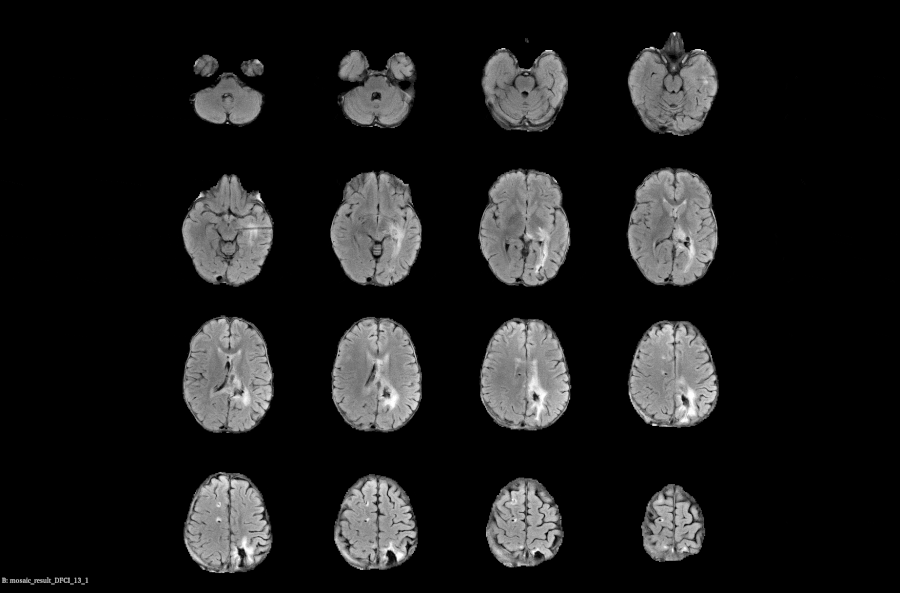

Voiant Hub 2.0 streamlines segmentation and tracking for semi-automated RECIST and volumetric automated RANO assessments, enhancing accuracy, consistency, and compliance in tumor response and tumor burden evaluation.

Voiant brings deep therapeutic insight and operational excellence to Phase I–IV oncology trials, including pivotal studies. We combined scientific expertise with AI-powered solutions to enhance imaging assessments—such as semi-automated RECIST and RANO—while supporting a broad range of tumor types, evaluation criteria, and imaging biomarkers with clarity and confidence.

- RANO; mRANO, RANObm; RANO 2.0